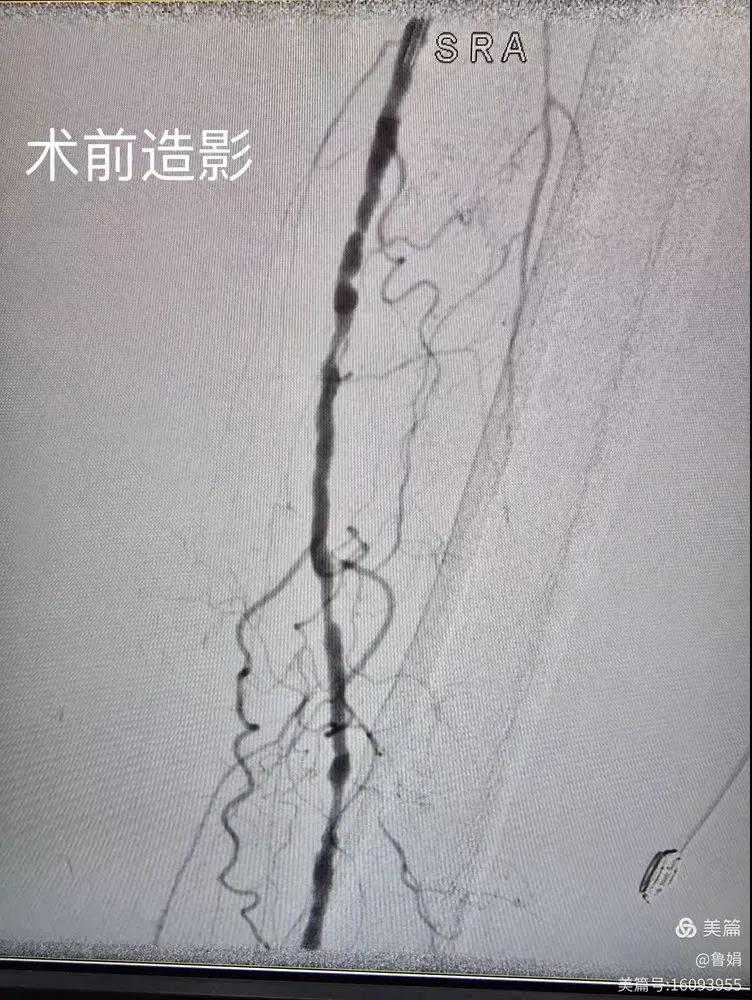

據(jù)悉,該患者,女,73歲,下肢動脈硬化閉塞癥,“以靜息痛,間歇性跛行”入院,CTA評估:股淺動脈,腘動脈間斷性多段重度狹窄,外二科血管外科團隊根據(jù)患者病情,結(jié)合檢查結(jié)果,經(jīng)過科室會診后,決定對該病人行介入治療。手術由周創(chuàng)業(yè)副主任與北大一院血管外科專家郭宏杰教授聯(lián)合開展,對股淺動脈,腘動脈重度閉塞段行血管開通+藥涂球囊擴張成形,術后狹窄明顯緩解,血流恢復!